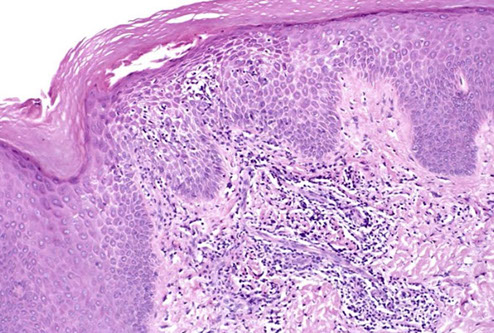

Cutaneous lymphoid hyperplasia in a 72-year-old man who presented with several purple-brown plaques on his cheeks and temples. A, The nodular infiltrate extends through the dermis with sparring of the overlying epidermis. B, It is characterized by scattered follicles with well-defined, reactive-appearing germinal centers, some of which have surrounding mantle zones. Many CD20-positive B cells are in the reactive follicles (C), and more numerous CD3-positive small T cells are present in the interfollicular areas (D). B-cell clonality studies (not shown) were negative for a clonal IGH or IGK gene rearrangement. [19]